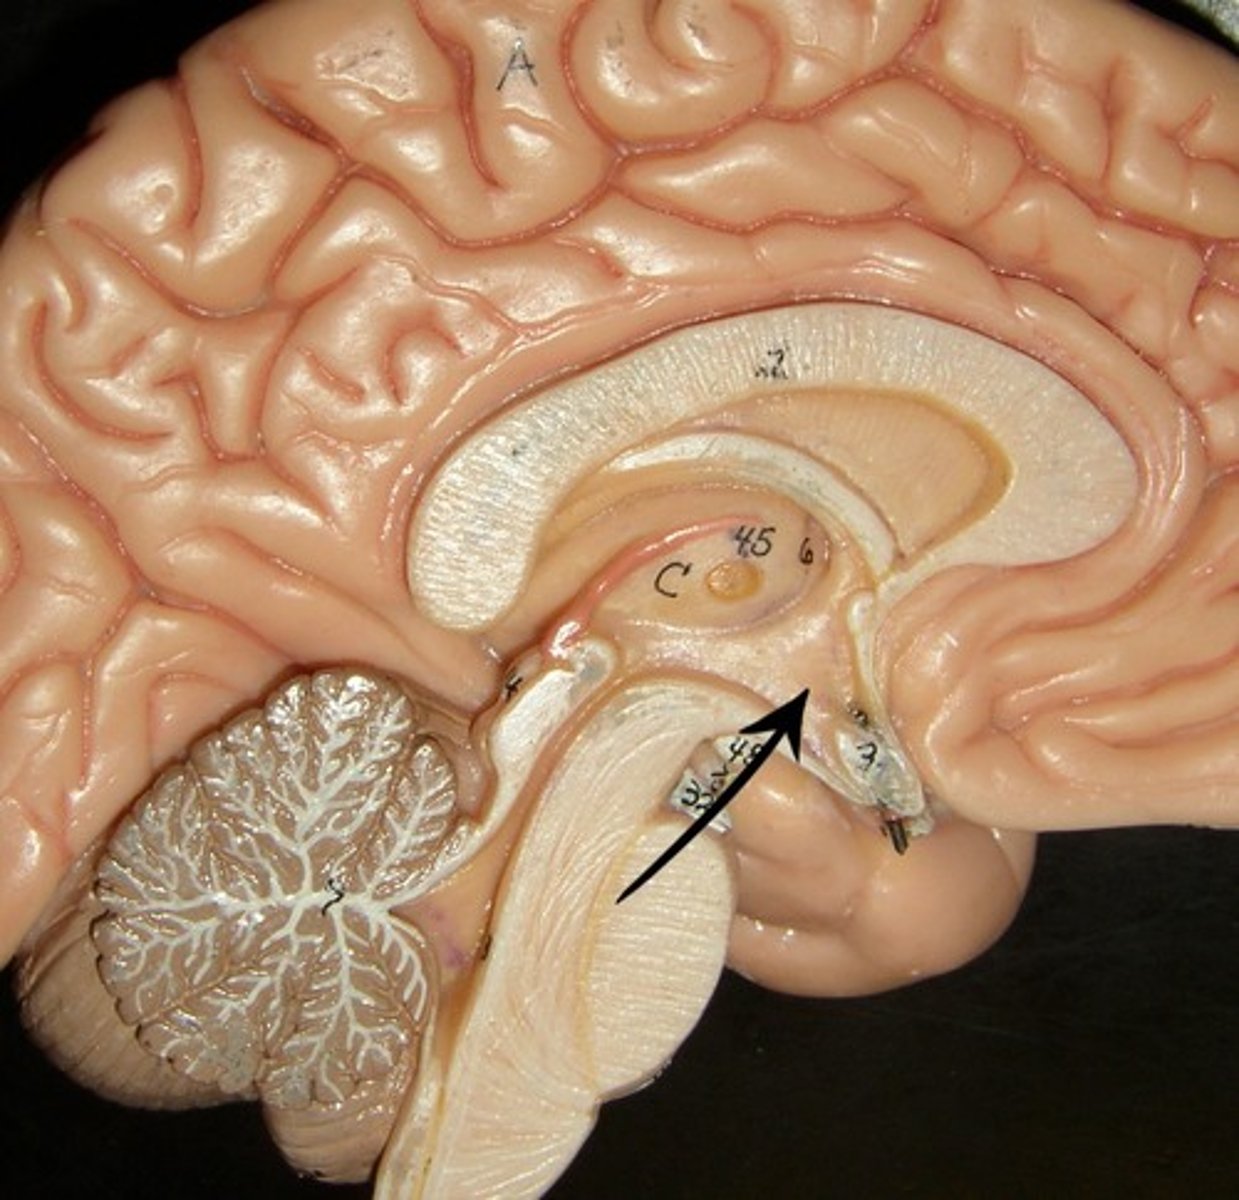

cerebral peduncle